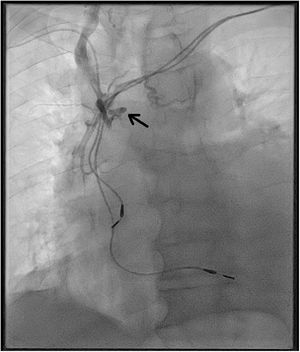

Tras instaurar tratamiento deplectivo mejoró significativamente el edema en miembros inferiores, pero persistió la disnea, así como el edema en miembros superiores, cara y cuello. Ante la sospecha de SVCS, se realizó una tomografía de tórax (sin contraste por deterioro función renal con niveles de creatinina de 2,7 mg/dL) que mostraba derrame pleural y pericárdico con una VCS conservada sin imágenes de compresión extrínseca. En el procedimiento para la inserción periférica de un catéter venoso central bajo radioscopia solicitado por fines terapéuticos, se identifica de forma casual la imposibilidad de avanzar a la VCS debido a existencia de trombosis en dicha localización (fig. 1). El cuadro fue interpretado como una trombosis de la VCS asociada a los cables del marcapasos. Se inició tratamiento anticoagulante y se intensificó el tratamiento diurético, mejorando progresivamente el edema asociado al SVCS y la disnea, mejoría que persistió en los sucesivos controles ambulatorios tras los seis meses del alta.